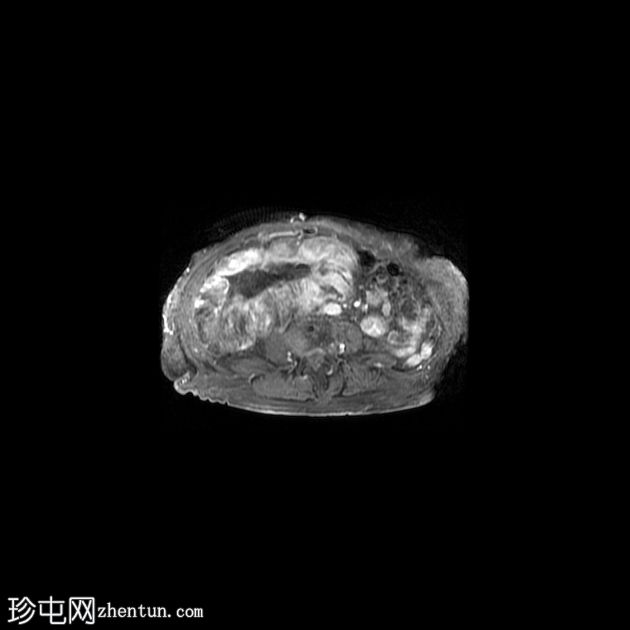

4.jpeg

冠状位

SSFSE

右髂窝移植肾不规则且受压,肾周可见巨大分叶状肿块,T2呈高信号,并进行性不均匀强化。这是黏液样变性的典型表现。